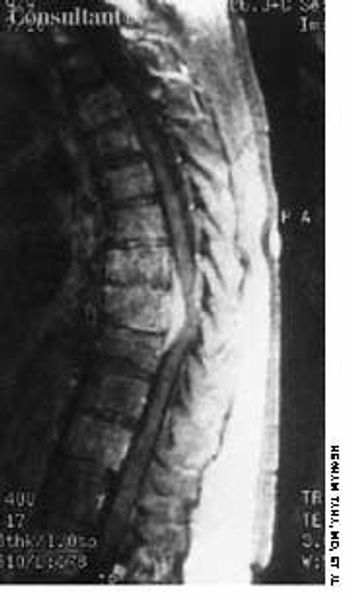

Back pain and weakness of both legs had bothered this 60-year-old woman for 1 week. Left breast cancer, stage 2, had been diagnosed 2 years before, and subsequently she underwent a lumpectomy followed by chemotherapy and radiation therapy.